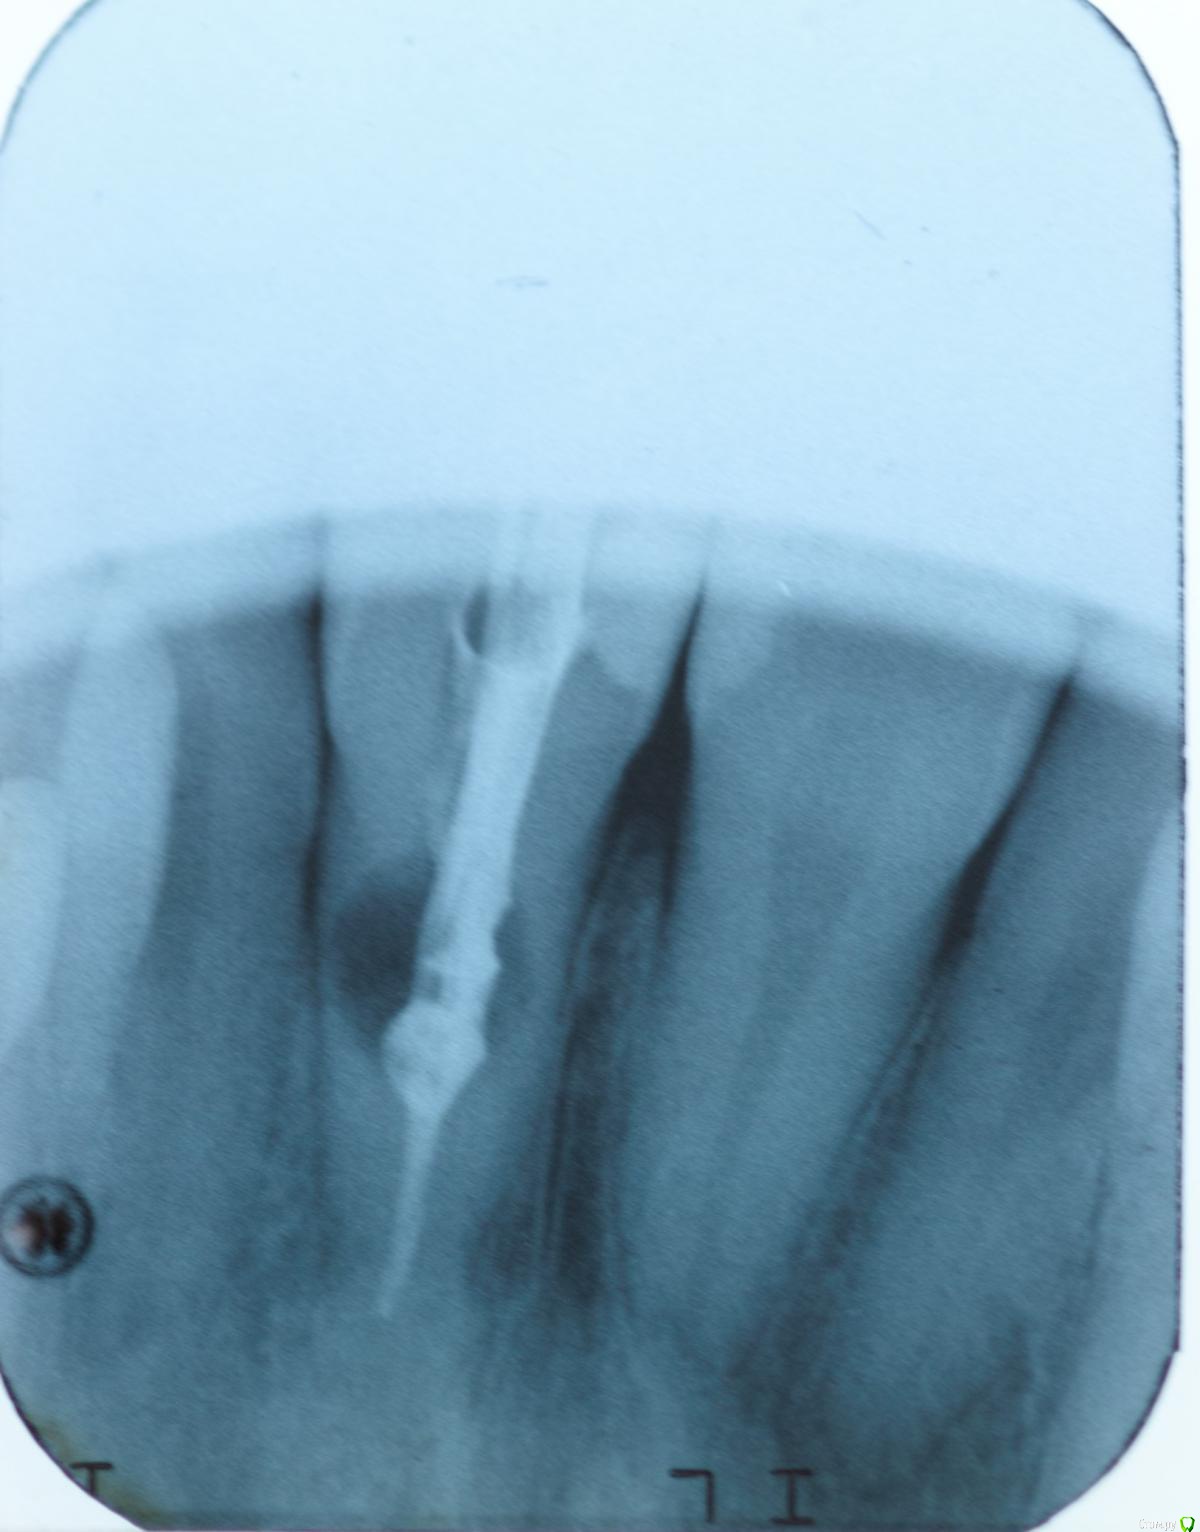

skeettrap Опубликовано 5 апреля, 2016 Автор Поделиться Опубликовано 5 апреля, 2016 (изменено) Латеральная конденсация. В очаге резорбции - МТА. Изменено 5 апреля, 2016 пользователем skeettrap Ссылка на комментарий

vse32 Опубликовано 7 июня, 2016 Поделиться Опубликовано 7 июня, 2016 У внутренних резорбций самый предсказуемый прогноз. Главное вычистить всю органику из канала и зоны резорбции. Тогда процесс остановится.Минус, если резорбция перфарирующая. Но и здесь все зависит от площади перфорирования и аккуратности. Самое сложное в таких случаях - запломбировать канал за зоной резорбции.Поздравляю. Ссылка на комментарий